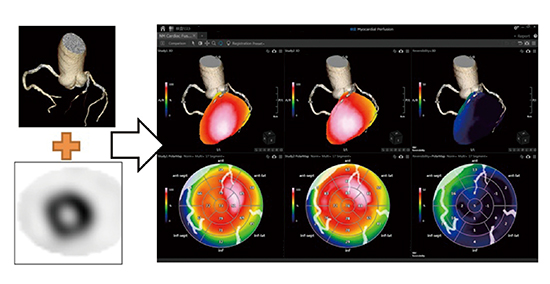

■冠動脈CT画像と心筋SPECTのフュージョン「NM Cardiac Fusion」

フュージョン用アプリケーションの一つであるNM Cardiac Fusionでは,冠動脈CT画像とSPECT画像の3Dフュージョン表示が可能である。冠動脈の状態(走行・狭窄や石灰化の有無)と心筋血流の状態(虚血・梗塞の有無)を同時に観察することで,責任血管の判定・治療方針の決定・被検者への説明に効果が期待できる(図5)。

また,本アプリケーションでは,ポーラーマップ解析画像も冠動脈CT画像とフュージョン可能で,被検者自身の冠動脈CT画像をオーバーレイ表示することで,複雑な血管走行をポーラーマップ解析画像上でも容易に把握できる。もちろん,ポーラーマップ解析はreversibilityやwashoutといった各種の解析に対応している。

図5 NM Cardiac Fusion使用画像

(画像ご提供:鹿児島大学様)